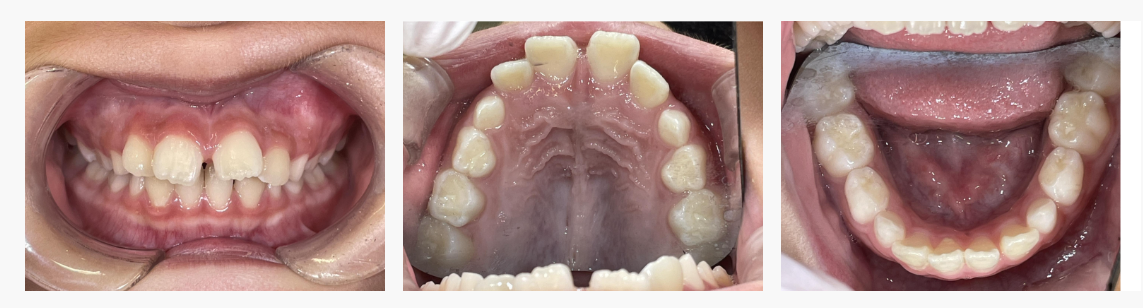

▼ After(治療後)

◆ 治療の結果

マイオブレイスとプレオルソによる成長誘導と機能改善により、

・前歯の突出感が軽減

・歯並びのガタつきが改善

・将来的に安定しやすい噛み合わせへ

といった変化がみられました。

成長期だからこそ可能な改善です。